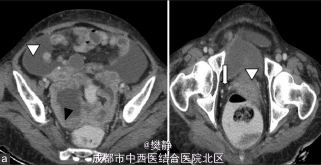

妇科检查提示直肠子宫陷凹可触及不规则结节,而双侧附件和子宫、宫颈未发现病变 CA-125常 B超,CT提示有腹水和直肠子宫陷凹、肠系膜的结节

诊断为盆腔肿块 行全子宫切除+网膜切除+腹膜活检

术后病理诊断为原发性腹膜的乳头状浆液性肿瘤